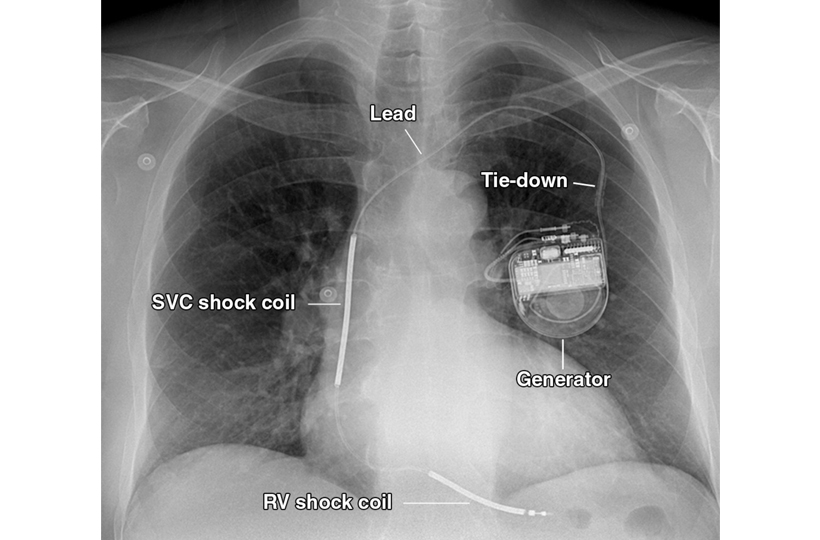

An AICD is a small device implanted under the skin, connected to your heart through thin wires (leads). It works by detecting dangerous arrhythmias and automatically delivering electrical shocks or pacing signals to correct them, protecting you from life-threatening cardiac events.